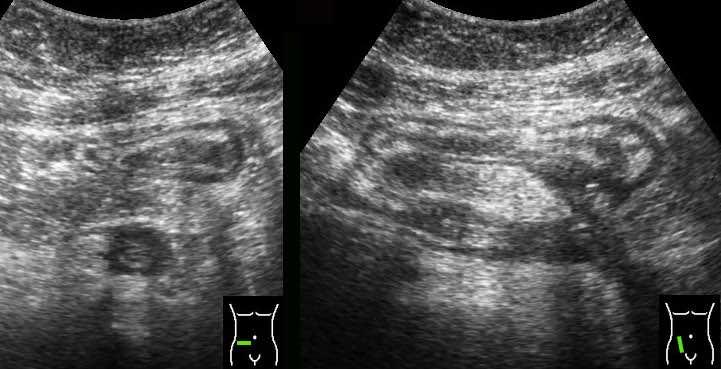

Sự khác biệt về kích thước và khả năng bị ép xẹp của hồi tràng bình thường (bên trái) và hồi tràng bị tổn thương do Crohn trong quá trình ép dần từng bước.

Sử dụng kỹ thuật ép dần từng bước, hai đoạn ruột kề nhau được ép vào cơ thắt lưng chậu.

Đoạn ruột phía trước là bình thường và dễ dàng bị ép xẹp, trong khi quai ruột bị Crohn hầu như không thể bị ép xẹp.

Đo độ dày thành ruột được thực hiện tốt nhất và có tính tái lập cao nhất trong khi ép, như ở đây trên một người bình thường (bên trái) và ở một bệnh nhân mắc bệnh Crohn (bên phải).

Các phép đo được thực hiện từ bờ ngoài của lớp cơ đến phía đối diện, sau đó chia cho 2, cho kết quả độ dày thành lần lượt là 1,5 mm và 6,5 mm đối với hồi tràng bình thường và hồi tràng Crohn.